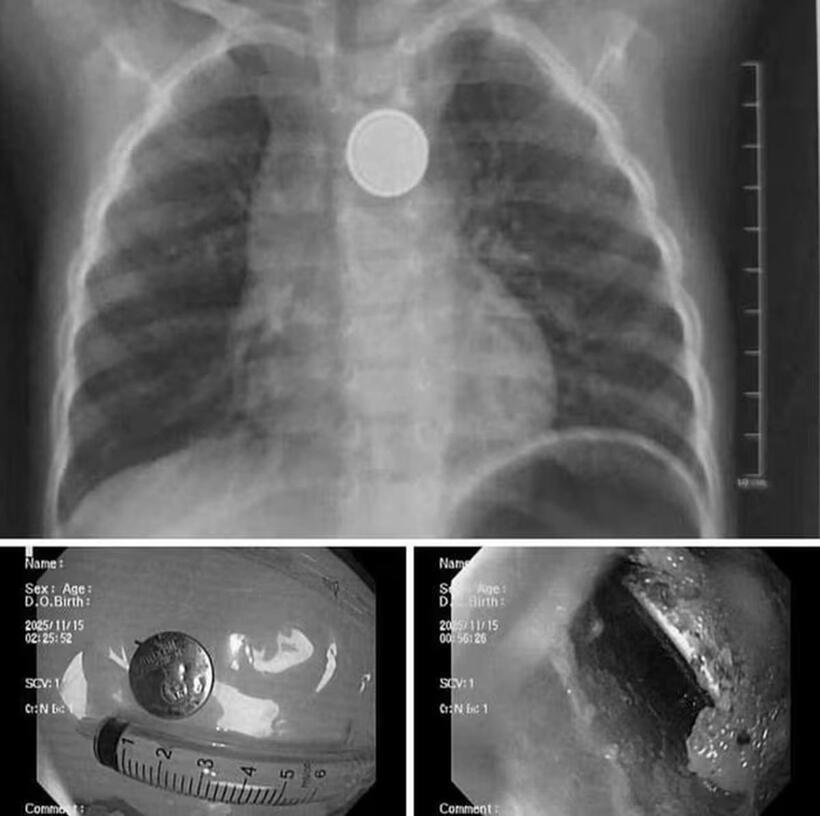

Theo Người đưa tin, Bệnh viện Nhi Hải Phòng cho biết, đơn vị vừa tiếp nhận và xử trí một ca cấp cứu nguy hiểm vì nuốt phải pin cúc áo.

Bệnh nhi là bé trai 32 tháng tuổi được gia đình đưa đến viện ngay sau khi phát hiện đã nuốt phải viên pin cúc đồ chơi. Rất may, gia đình phát hiện sớm và đưa trẻ đến bệnh viện trong khoảng 1 giờ sau khi nuốt.

Dị vật là pin cúc áo trong thực quản trẻ. Ảnh: Người đưa tin.

Tại bệnh viện, các bác sĩ đã tiến hành chụp X-quang, kết quả cho thấy dị vật kẹt tại thực quản.

Ê-kíp nội soi cấp cứu đã nhanh chóng tiến hành gắp thành công viên pin ra ngoài. Dù được cấp cứu sớm song qua quan sát trực tiếp, ê-kíp nội soi ghi nhận có vùng ăn mòn, gây loét thực quản.

Các bác sĩ cho biết, pin cúc đồ chơi có thể gây tổn thương nghiêm trọng chỉ trong thời gian rất ngắn. Do đó, việc lấy dị vật kịp thời giúp hạn chế nguy cơ thủng thực quản, nhiễm trùng trung thất và các biến chứng nặng khác.

Bệnh viện khuyến cáo phụ huynh cần giữ pin và các thiết bị dùng pin xa tầm với của trẻ. Khi nghi ngờ trẻ nuốt pin phải đưa đến bệnh viện ngay, không được tự gây nôn vì tổn thương do pin có thể xảy ra trong vài phút, ngay cả khi trẻ được đưa đi cấp cứu rất sớm.